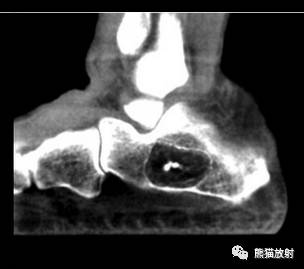

↓ 跟骨骨内脂肪瘤

IA型 ↓ 骨内脂肪瘤